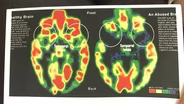

Patricia Tilley of the NH Department of Health and Human Services describes the impact of adverse early experiences on growth and development. Home visiting programs for new moms and babies can help address some of these issues.